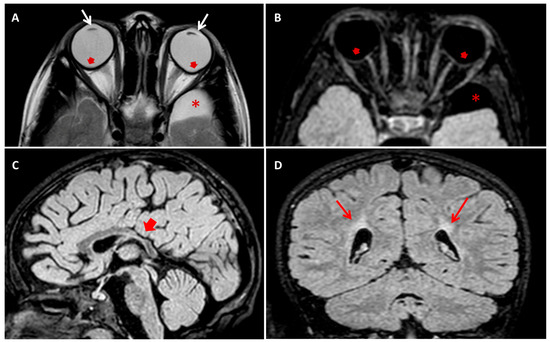

The boy was born at 27 weeks after a physiological pregnancy via cesarean delivery. He was the first child of healthy and unrelated parents (Figure 1A). The patient’s family history was unremarkable for intellectual disability and congenital anomalies. Apgar scores at 1 and 5 min were 4 and 7, respectively. Data regarding the perinatal history are limited because the child was born at a different care institution. At birth, the newborn was admitted to the neonatal intensive care unit for prematurity and required some ventilatory support in the first days of life. During the first week of life, systemic physical examination revealed bilateral lens opacities. Ophthalmologic examination confirmed the presence of bilateral congenital nucleo-cortical cataract, which underwent surgical correction in the first weeks of life. Other ocular features included microphthalmia, microcornea, astigmatism, nystagmus, and strabismus. Additional investigations, including ultrasound of the abdomen, echocardiogram, and infectious and metabolic (including galactosemia) work-up were all normal. Since his early infancy, the patient presented with diplegia. Cognitive and language development was reported as normal, as well as his social communication and interaction abilities. At the age of 2 years, brain magnetic resonance imaging (MRI) was performed and reveled an enlargement of the supratentorial portion of the ventricular system due to the enlargement of posterior horns, and middle cranial fossa arachnoid cysts were seen. These radiological findings were attributed at that time to possible perinatal ischemic injury due to prematurity. A standard motor rehabilitation program was set up. At 5 years of age, the child presented an episode characterized by generalized hypertonia, nystagmus, and bruxism, lasting a few minutes. Initially, low-grade fever and earache were considered as causative of the abovementioned symptoms. During the subsequent months, interactional skills started regressing and the development of obsessive-compulsive behavioral pattern was observed. At 8 years of age, a progressive loss of the previously acquired motor, language, and adaptive skills occurred, and the child exhibited psychic and/or motor agitation and either self-reported or not self-reported aggressive behavior. At the physical examination, the patient presented small teeth with abnormal implant (Figure 1B). Signs of vegetative nervous system activation, such as palmar and plantar hyperhidrosis and hypersalivation, were noticed. Electroencephalogram during wakefulness did not show significant abnormalities. A follow-up brain MRI scan was consistent with periventricular leucomalacia, with no more detectable enlargement of ventricular system. Risperidone, gamma-amynobutiric acid, and melatonin were started, with poor benefits. Autoimmunity work-up showed raised serum levels of anti-basal ganglia antibody (ABGA), but their dosage in the cerebrospinal fluid was negative. Autoimmunity investigation of cerebrospinal fluid showed non-specific results, finding the presence of antibodies directed towards antigens of 80 and 110 kDa, not yet identified and of uncertain pathogenetic role. Further autoimmunity (anti-nuclear, extractable nuclear antigens, lupus anticoagulant, anticardiolipin, and antiphospholipid antibodies—on serum—and anti-glutamic acid, anti-N-methyl-D-aspartate receptor, anti-Aquaporin 4, and anti-voltage-gated potassium channels—both on serum and liquor-) and metabolic (serum and urinary aminoacids, Fehling test, and ceruloplasmin) work-up were all normal. Mitochondrial encephalopathy with lactic acidosis and stroke-like episodes (MELAS syndrome) was ruled out based normal serum lactate and pyruvate levels, negative mitochondrial DNA testing, and absence of POLG intragenic variants in exome sequencing data. Karyotype and array-comparative genomic hybridization (CGH) were normal. A preliminary diagnosis of autoimmune encephalitis was hypothesized, and oral steroids for three months and intravenous immunoglobulin therapy were attempted, with no clinical improvement. At 9 years of age, a new MRI scan confirmed previous findings and additionally detected the deformation of both eyeballs at the rear portions (Figure 2).

Figure 2. (A) Axial T2 turbo-spin echo (TSE) and (B) axial T2 fluid attenuated inversion recovery (FLAIR) brain MRI images showing bilateral crystalline lens thinning (white arrows in (A)) and circumscribed outpouching along the posterior aspect of the ocular bulbs, temporal to the optic disc (red arrows in (A,B)). Note a well circumscribed left temporo-polar arachnoid cyst (* in (A,B)). (C) Sagittal T2 FLAIR and (D) Coronal T2 FLAIR brain MRI images showing thinning of posterior trunk of corpus callosum (red short arrow in (C)) and bilateral deep paratrigonal white matter hyperintensity due to periventricular leukoencephalopathy (red arrows in (D)).

Although the central anomalies identified by brain MRI and characterized by corpus callosum dysgenesis (and periventricular leukoencephalopathy) remain largely unexplained, the high expression of NHS in certain brain regions (e.g., fronto-parietal cortex, corpus callosum) supports a potential role of this gene in brain development and function.